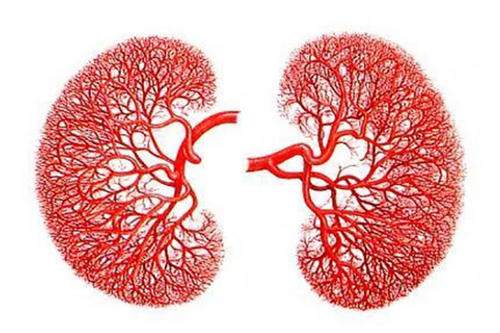

011第一种治疗法:通过手术治疗来治疗这个疾病,但是通过手术治疗一般主要是应用在身体素质体能比较好的老年人,而且要注意手术中出血症状,因为涉及到肾癌属于多血管肿......